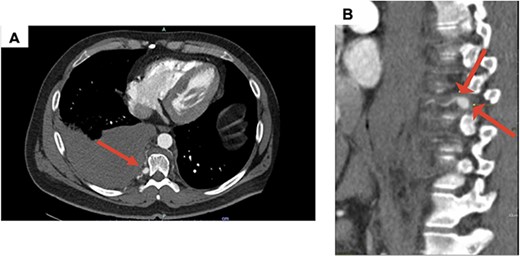

A 41-year-old adult with NF1, presented with a spontaneous right-sided hemothorax after strenuous exercise associated with a presyncopal episode at home. A CT chest angiogram revealed a moderate-to-large right side hemothorax and a 13-mm fusiform aneurysm of the right posterior T9 intercostal artery without active extravasation (Fig. 1A and B). Due to concern for aneurysmal rupture, he was transferred to a tertiary care center.

(A) Axial CT with contrast demonstrating a large right hemothorax on presentation; (B) sagittal CT with contrast, arrows showing T9 intercostal artery aneurysm.